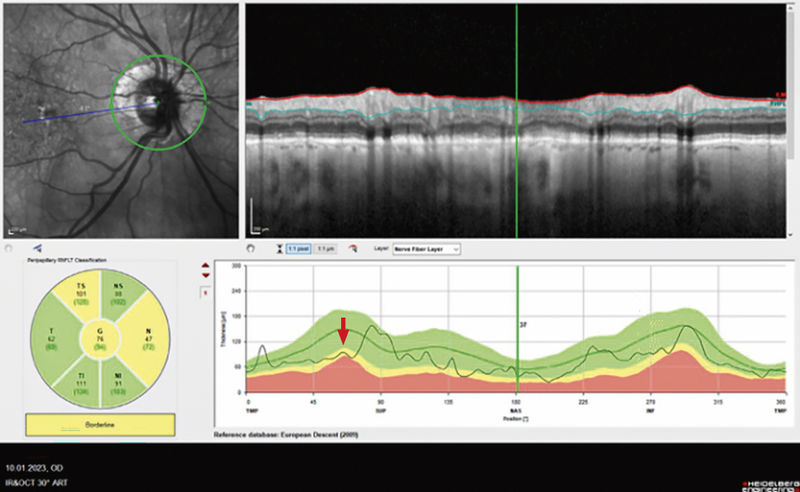

Abbildung 6: Optische Kohärenztomografie (OCT) des rechten Auges mit beginnendem Sehnervenschaden (Ausdünnung der retinalen Nervenfaserschicht). Diese Diagnostik ermöglicht die quantitative Messung der Nervenfaserschichtdicke am Sehnervenkopf um strukturelle Abweichungen von der Norm, sowie Verlaufsveränderungen frühzeitig zu objektivieren.

Fall 2: Therapeutische Optionen beim primären Offenwinkelglaukom

Ein 88-jähriger Patient mit primärem Offenwinkelglaukom stellte sich mit der Frage nach operativer Versorgung bei einer Augeninnendruckdekompensation in der Sprechstunde vor. Die Erstdiagnose sei wenige Tage zuvor mit Augeninnendruckwerten von 42 mmHg am rechten Auge und 34 mmHg am linken Auge gestellt worden. Beidseits lagen die Werte deutlich über dem Normbereich von 10 bis 21 mmHg. Beidseits bestand aufgrund einer Katarakt eine Visusminderung auf 0,5 rechts und 0,4 links. In der klinisch-ophthalmologischen Untersuchung zeigte sich ein offener Kammerwinkel, funduskopisch die Netzhaut zirkulär anliegend bei einer trockenen, altersbedingten Makuladegeneration und rechts mehr als links beginnender glaukomatöser Papillenexkavation. In der durchgeführten optischen Kohärenztomografie-Aufnahme der Papille konnte der klinische Befund mit einer beginnenden Ausdünnung des retinalen Nervenfaserpolsters ebenso objektiviert werden (siehe roter Pfeil in Abbildung 6, rechtes Auge dargestellt). Anamnestisch bestünden keine weiteren Vorerkrankungen.